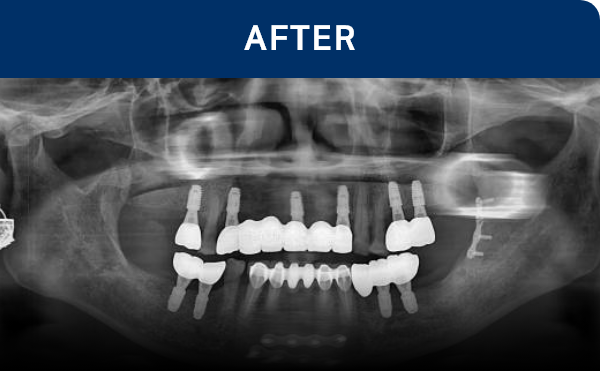

전후가 명확한 결과, 그 결과가

곧 신길플란트치과의 신뢰입니다.

불편함 없이 웃고, 걱정 없이 드실 수 있도록 임플란트로 일상의 편안함을 되찾아드리겠습니다.